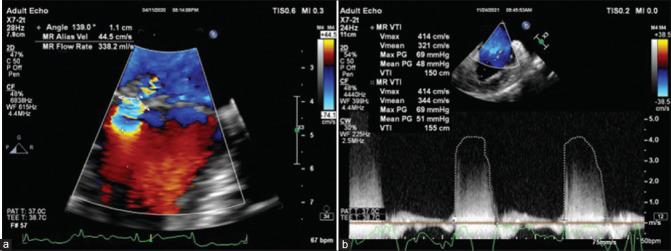

Intraoperative quantification of mitral regurgitation (MR) is sometimes necessary to quantify the severity of incidentally detected MR during cardiac surgeries. We aimed to compare and correlate the regurgitant volume (Rvol) and regurgitant fraction (RF) using 2D proximal isovelocity surface area (PISA) and 3D vena contracta area (VCA) with the 3D volumetric method and the integrated multiparametric approach.

A prospective observational study was conducted on 37 patients undergoing mitral valve surgery for MR. Intraoperative quantification of the severity of MR was done using 2D PISA and 3D VCA methods and was compared with the 3D volumetric method. All three methods were compared with the integrated multiparametric method to obtain cutoff values for identifying severe MR.

The correlation coefficients for Rvol with VCA and PISA with the 3D volumetric method were 0.688 and 0.58, respectively. VCA and PISA overestimated the Rvol (VCA = 77.93 ± 27.82 ml, PISA = 76.13 ± 19.25 ml) compared to the 3D volumetric method (66.12 ± 20.30 ml); the RF by the three methods was comparable. Using the receiver operating characteristic-area under curve (AUC) comparing Rvol by these methods with the integrated multiparametric method, the 3D volumetric method performed the best.

心脏手术中有时需要对二尖瓣反流(MR)进行术中定量,以评估偶然发现的MR的严重程度。我们旨在使用二维近端等速表面积(PISA)和三维瓣口收缩期面积(VCA),将反流容积(Rvol)和反流分数(RF)与三维容积法和综合多参数方法进行比较并建立相关性。

对37例因MR接受二尖瓣手术的患者进行了一项前瞻性观察研究。使用二维PISA和三维VCA方法对MR严重程度进行术中定量,并与三维容积法进行比较。将这三种方法与综合多参数方法进行比较,以获得识别严重MR的截断值。

Rvol与VCA以及PISA与三维容积法的相关系数分别为0.688和0.58。与三维容积法(66.12±20.30ml)相比,VCA和PISA高估了Rvol(VCA=77.93±27.82ml,PISA=76.13±19.25ml);三种方法测得的RF相当。通过比较这些方法测得的Rvol与综合多参数方法的受试者工作特征曲线下面积(AUC),三维容积法表现最佳。